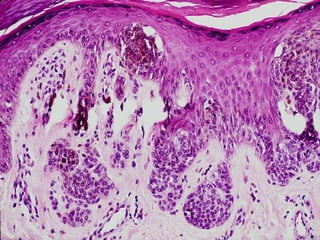

• #43 Keratoacanthoma, the MAIN lesion to differentiate from squamous cell carcinoma

• #44 Keratoacanthoma, the MAIN lesion to differentiate from squamous cell carcinoma

• #45 Keratoacanthoma, the MAIN lesion to differentiate from squamous cell carcinoma. What is a collarette? Is a collarette the classical feature which differentiates KAs from SCCs? Ans: YES